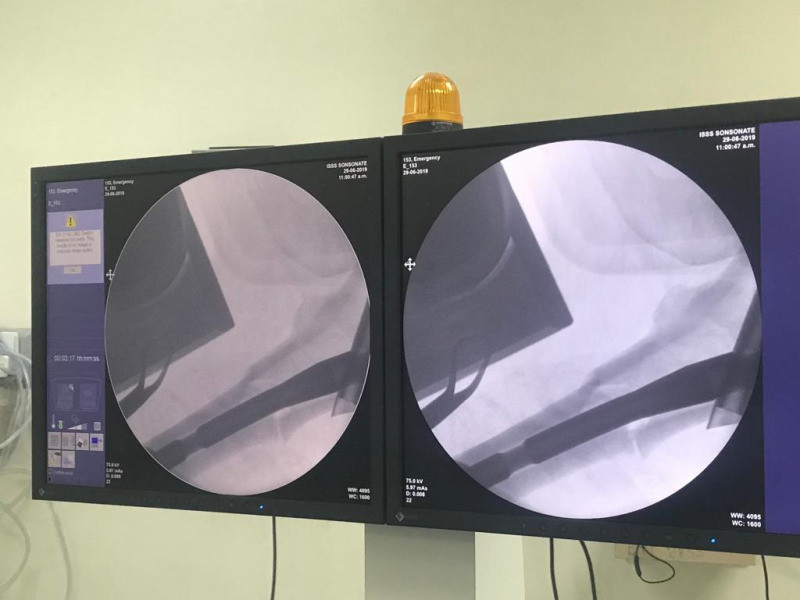

Imágenes de ortopedia y traumatología

Envíado por Dr. José Israel Flores Hernández